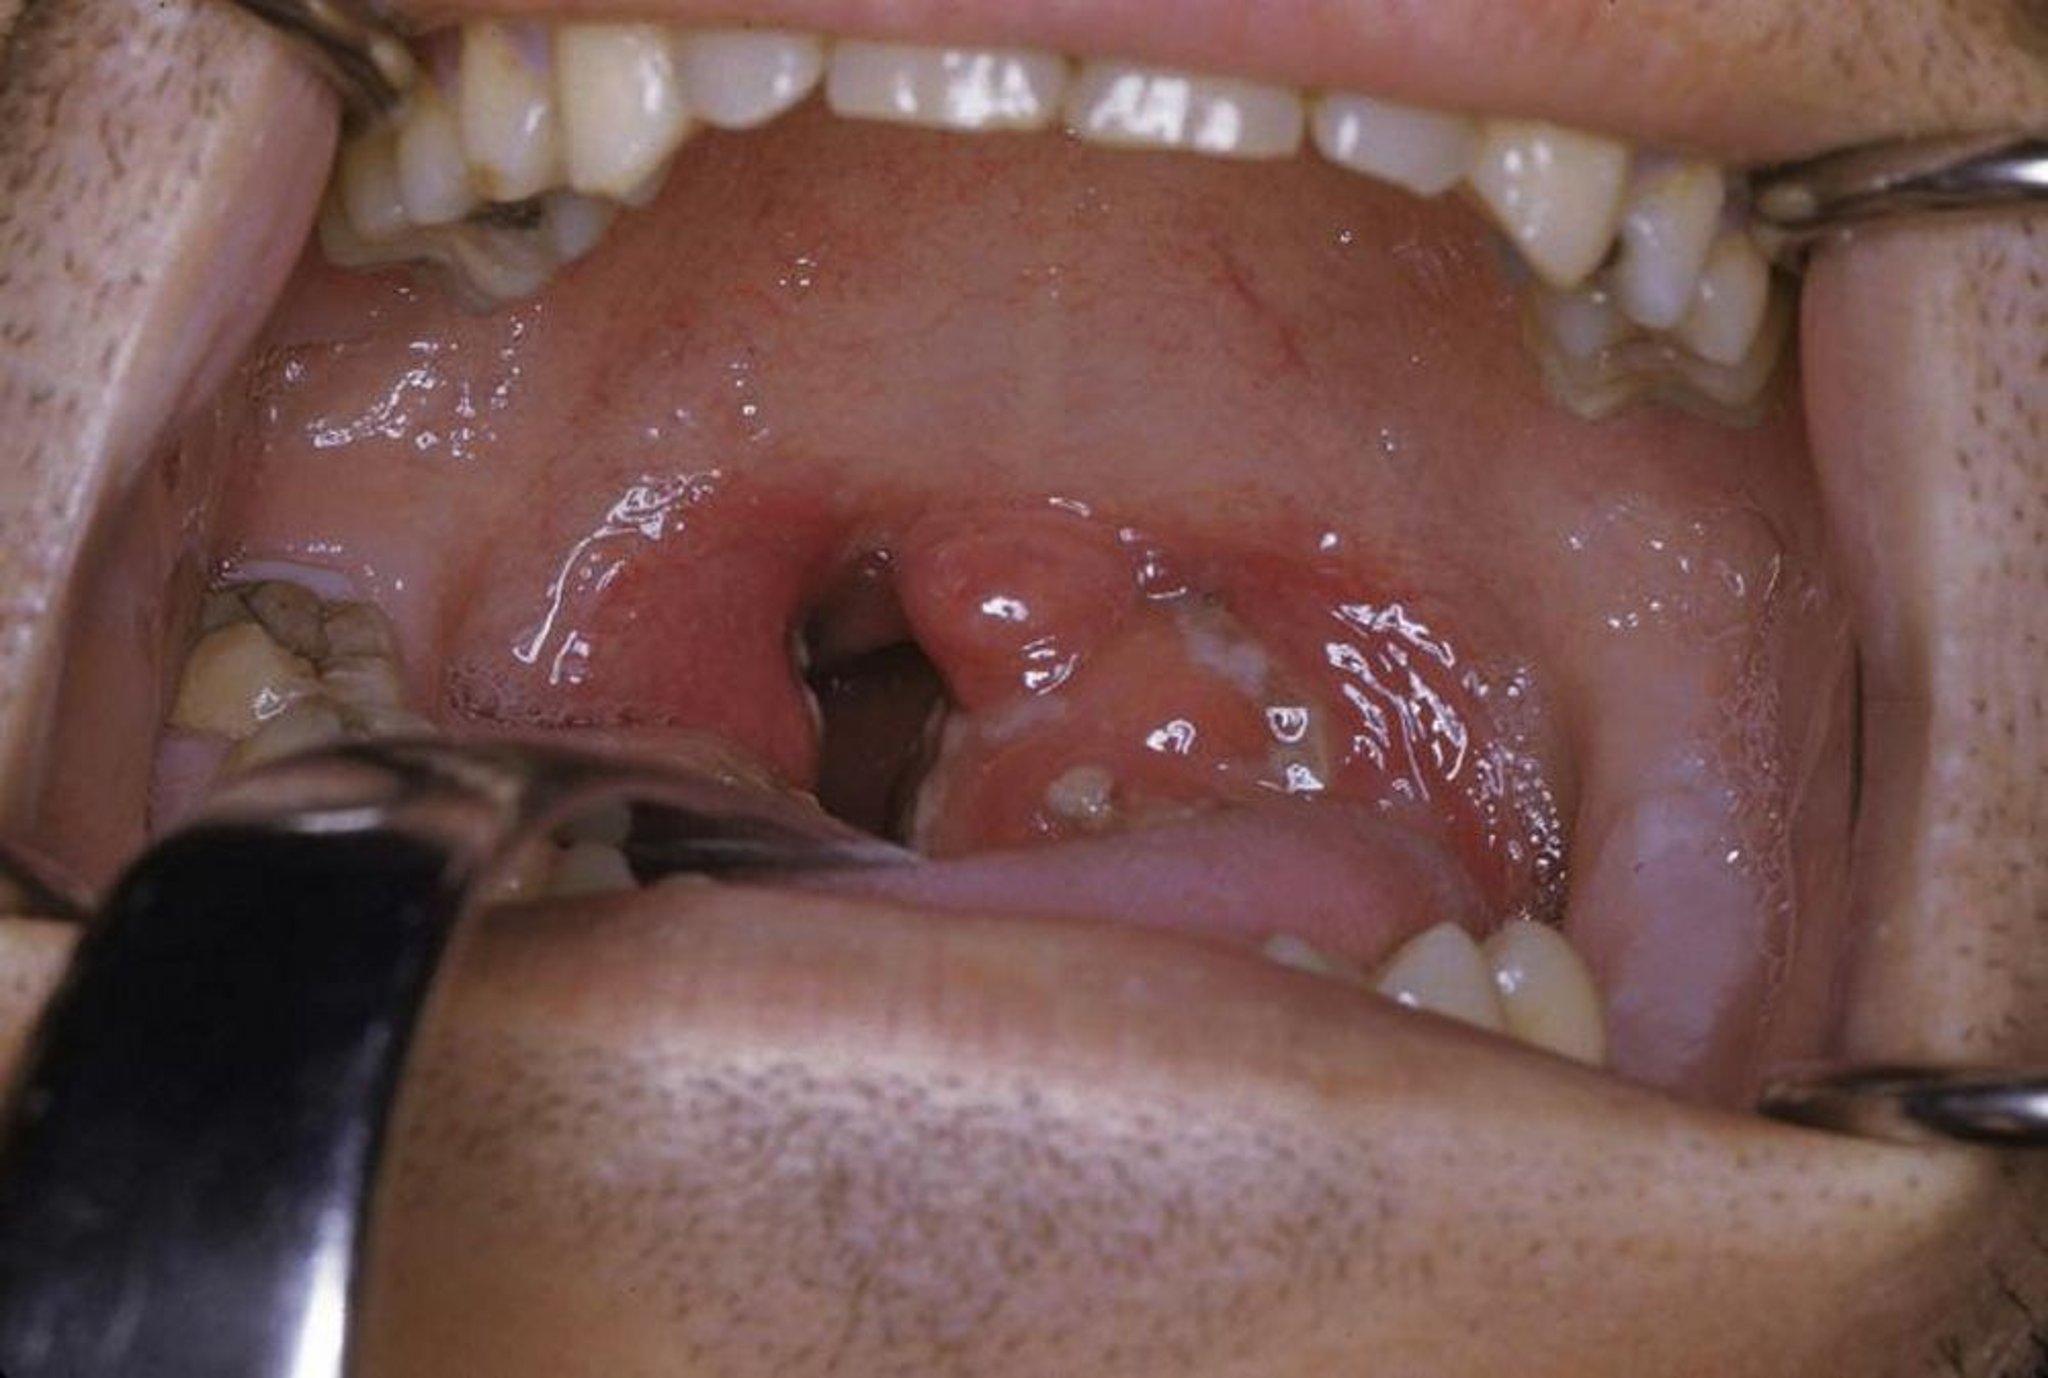

Острый тонзиллит

На данной фотографии показан острый тонзиллит с экссудатом и эритемой.

Фото предоставлено г-ном Кларенсом Т. (Clarence T.). Sasaki, MD.